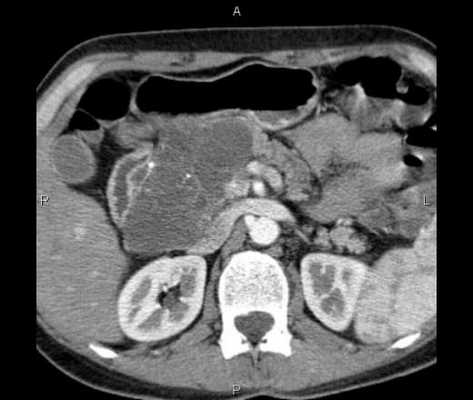

При УЗД: органы малого таза и брюшной полости без особенности. Асцита нет. Лимфатические узлы не увеличены. В толще передней прямой мышцы живота справа лоцируется двухузловое гипоэхогенное образование размером 98x64 мм, обычной звукопроводимости, с неровными четкими краями, болезненное при надавливании датчиком. Первоначально образование было расценено как межмышечная посттравматическая гематома. Проведенные КТ и МРТ не уточнили диагноз.